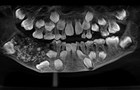

VOVVN - VOV.VN - Hình ảnh chụp X-quang cho thấy một cậu bé 7 tuổi ở Ấn Độ có đến 526 cấu trúc giống răng lớn nhỏ “chen lấn” nhau trong hàm.